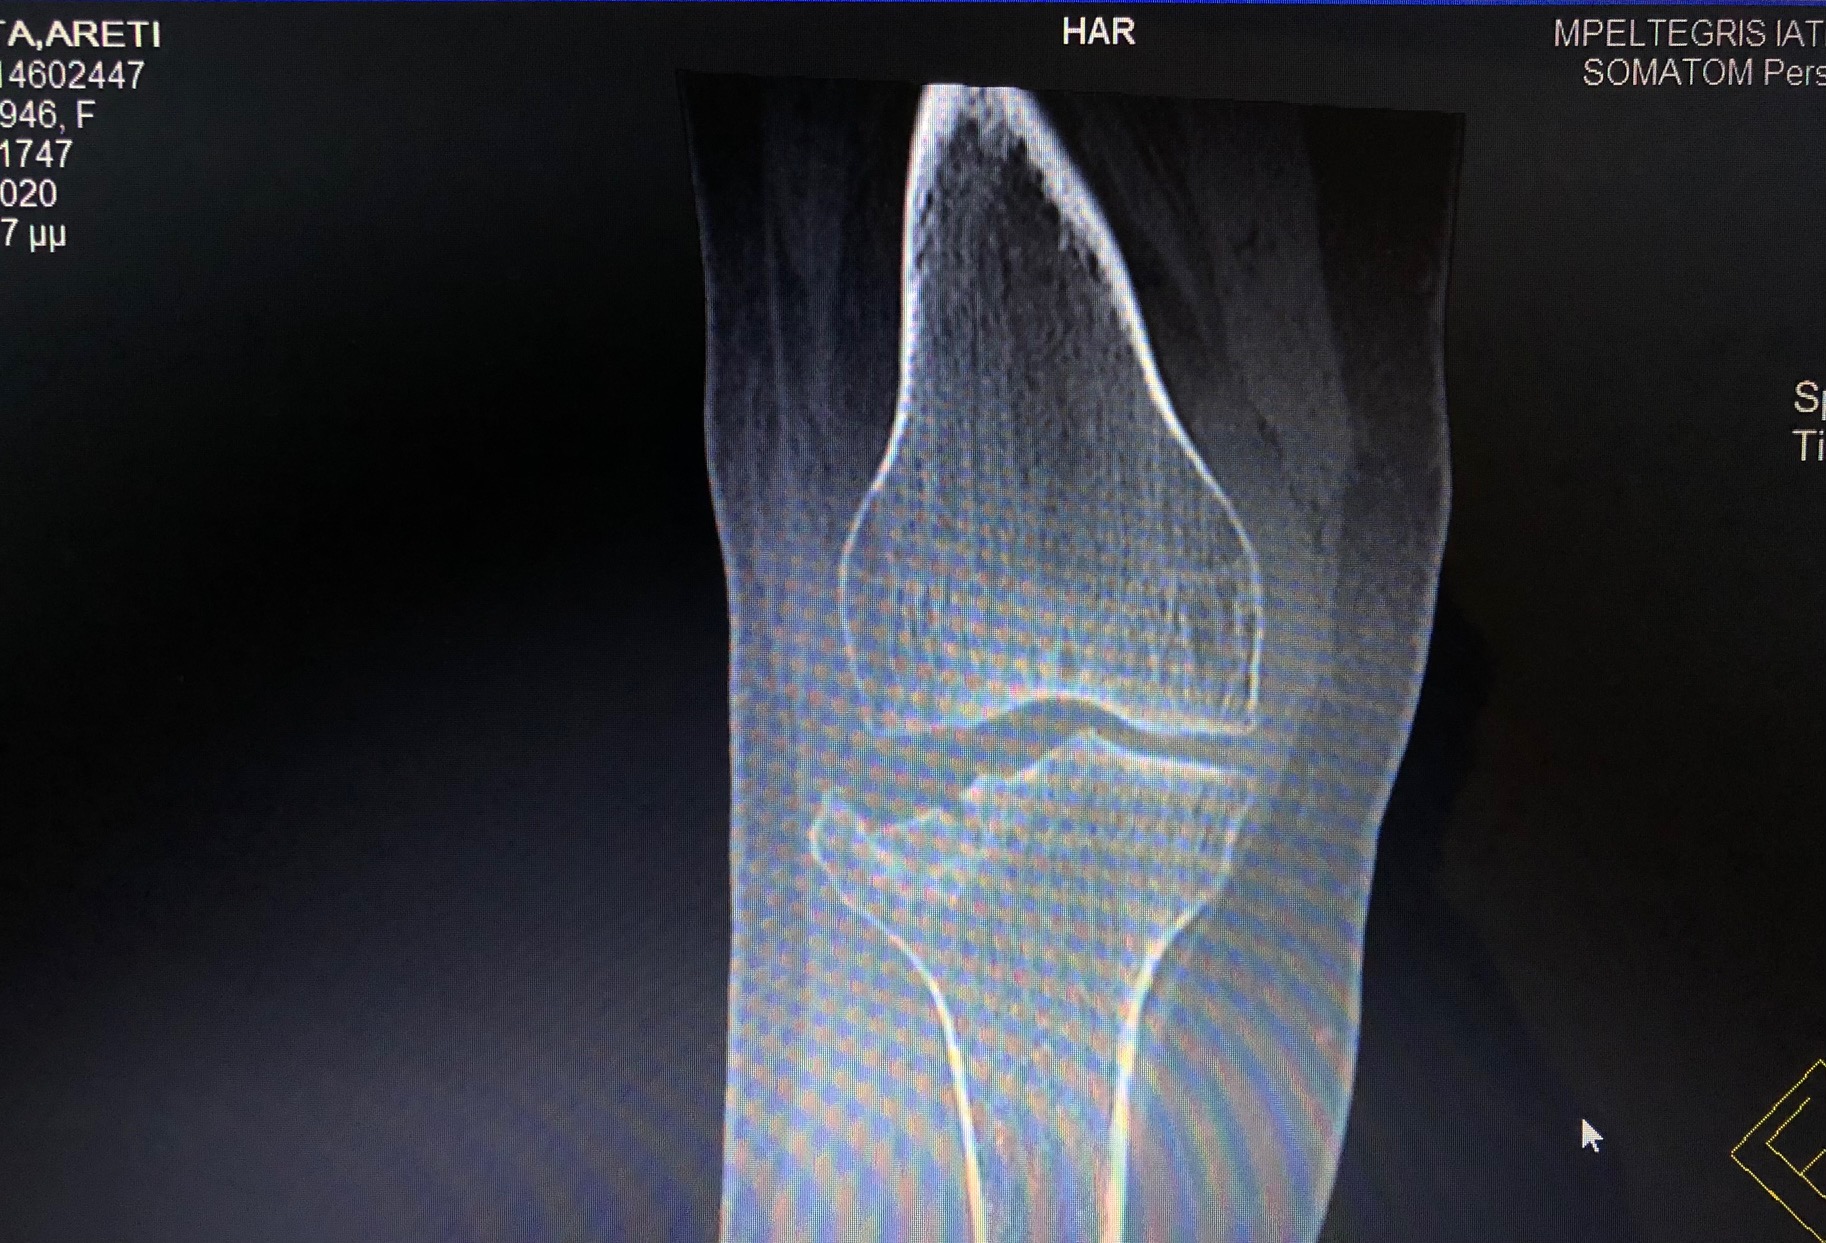

Η διάγνωση ενός κατάγματος κνημιαίου plateau πραγματοποιείται από έναν έμπειρο Ορθοπαιδικό. Αρχικά η λήψη ενός λεπτομερούς ιστορικού και η κλινική εξέταση του ασθενούς είναι απαραίτητα. Στην συνέχεια για την διάγνωση αλλά και την ταξινόμηση του κατάγματος είναι υποχρεωτική η διενέργεια ακτινολογικού ελέγχου. Ο έλεγχος αυτός περιλαμβάνει απλές ακτινογραφίες (φας, προφιλ και λοξές) ενώ πολλές φορές απαιτείται περαιτέρω διερεύνηση με αξονική τομογραφία για την πλήρη κατανόηση της μορφής του κατάγματος και τον σωστό προεγχειρητικό σχεδιασμό.

Ταξινόμηση καταγμάτων κνημιαίου plateau

Η ταξινόμηση που χρησιμοποιείται ευρέως από τους Ορθοπαιδικούς για τα κατάγματα του κνημιαίου plateau είνα αυτή του Joseph Schatzker: